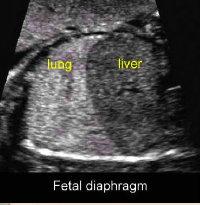

What are the sonographic finding of the diaphragm?

Hypoechoic compared to lung

Between lung/liver/spleen

Seen consistently after 20 weeks gestation

Note this longitudinal view of the thorax and abdomen & is early in the gestational age - the lungs are still hypoechoic compared to the liver

Note this longitudinal view of the thorax & abdomen that is later in the gestational age - the lungs are now hyperechoic compared to the liver